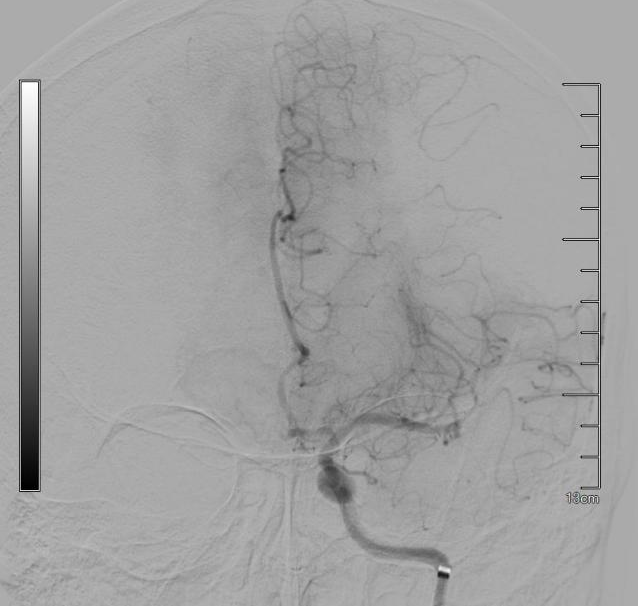

患者术后血管再通

术中,专家团队沉着应战、精准操作,凭借过硬技术与默契配合,从穿刺到血管成功再通仅用时11分钟,以“极速救治”完成了这场与死神的赛跑。术后,在医务人员密切监护和精心照料下,患者可基本独立下床活动,预后效果较好,悬在家属心中的“石头”终于落地。